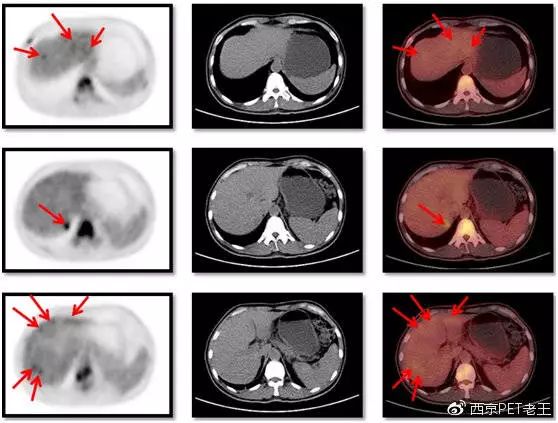

做完了PET/CT,我们先看看肝脏病变的情况(如下图):肝脏内和肝包膜区可见多个结节状、环状、条状葡萄糖代谢增高病灶(左侧列箭头),但CT图像上病变不明显(中间列),右侧列是PET/CT融合图像,不但能显示病灶的位置而且可以显示病灶的代谢情况。

从PET/CT图像上,我们判断为肝脏多发转移。除了肝脏,从图上我们还看到了多处骨头上有代谢增高,难道多个骨有转移?

患者肝脏病变的情况